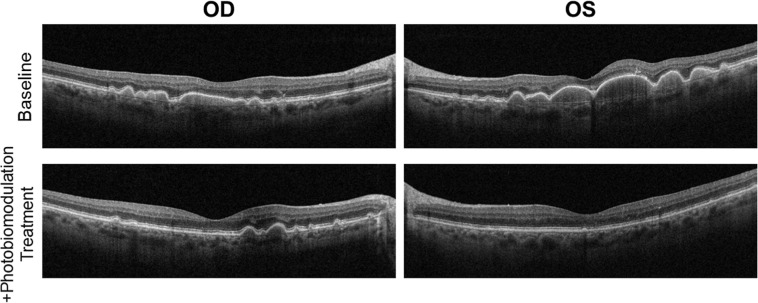

Introduction: This case report describes a finding of dramatic improvement in drusen volume and visual acuity in a 73-year-old patient diagnosed with dry age-related macular degeneration (AMD) undergoing daily home photobiomodulation alongside AREDS-2 supplements.

Case presentation: This is a retrospective review of a case presentation from 2023 to 2024. After 8 months of continuous home photobiomodulation, the patient's visual acuity improved from 20/30 to 20/20 in the left eye while the right eye stabilized at 20/25. The outer retina was preserved without signs of geographic atrophy, with a robust reduction in the total number and volume of drusen in both eyes, left greater than right, as shown with optical coherence tomography macular cross-sectional scans.